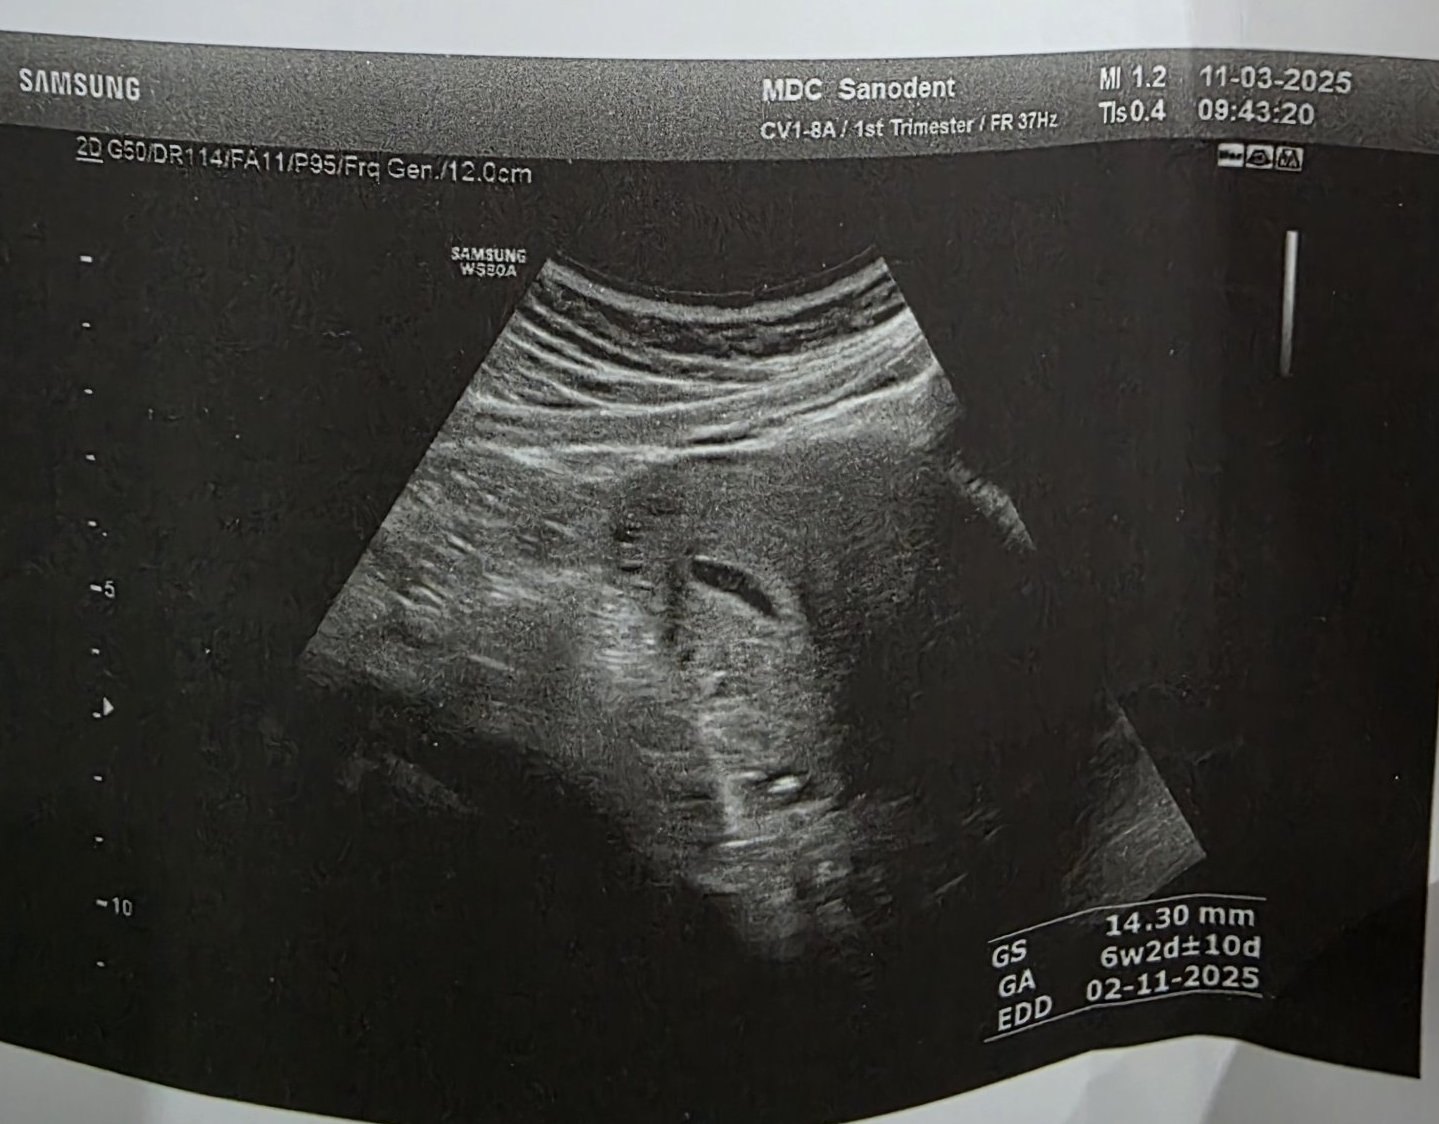

Какво представлява изображението от ехографията на 5-седмична и 2-дневна бременност?